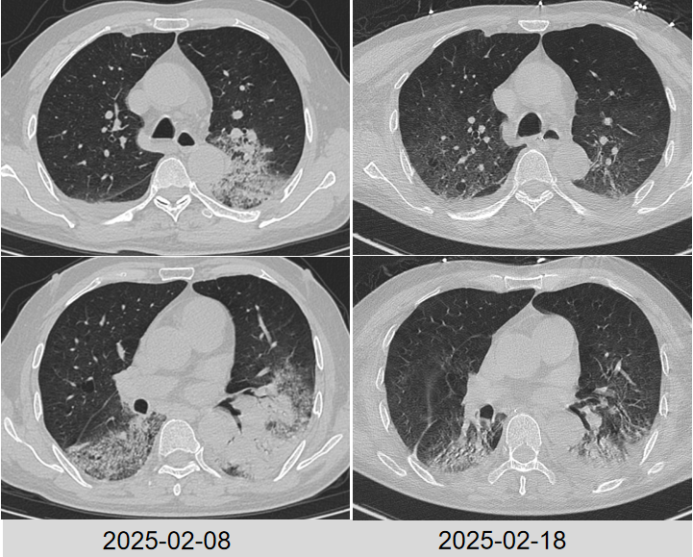

胸部CT2025-02-08(图1):双肺见大片状磨玻璃、实变影,以双肺下叶及左肺上叶明显,内见空气支气管征象,边缘模糊,考虑感染性病变可能,伴间质受累,合并其他待排双肺上叶少许小结节,多系炎性双肺少许小肺大泡。双侧胸腔少量积液,双侧胸膜增厚粘连心包少量积液可能主动脉壁及主动脉瓣区钙化纵隔及双肺门淋巴结增多、部分稍增大,部分伴钙化。扫及胸段食管稍扩张。

治疗后患者体温逐步恢复正常,炎症指标下降。复查胸部CT(2025-02-18)可见双肺炎症稍吸收(图3)

3  患者治疗前后胸部CT对比

202535日复查胸部CT病灶较前进展(图4),炎症指标有所回弹,以中性粒细胞升高为主,抗感染方案调整为哌拉西林他唑巴坦4.5 g q9h+奥环素300 mg qd po

4  患者复查胸部CT对比

2025312日患者氧合无明显改善,复查胸部CT示肺部病灶进展(图4)将抗生素方案调整为美罗培南+米卡芬净+莫西沙星,甲泼尼龙抗炎,无创呼吸机辅助通气。

普通病房治疗期间出现如下问题:患者经鼻高流量无法脱机,且逐步加重202535日和312日先后两次复查胸部CT,肺部影像学进展明显患者咳痰乏力,自拔管后即发现右侧肢体肌力下降,病理征阴性,头颅CT无异常。经肺康复与功能康复锻炼后咳痰能力、右侧肌力仍恢复欠佳2025313日膈肌功能评估:膈肌厚度0.14~0.16 cm,增厚分数下降,膈肌移动度下降

根据病原学结果,先后予以米卡芬净+美罗培南、哌拉西林他唑巴坦+环丙沙星头孢他啶阿维巴坦抗感染治疗2025324日拔管3月27日复查胸部CT提示肺部病变好转吸收(图5)。患者仍有明显咳痰困难,乏力,四肢肌力下降,经康复锻炼恢复欠佳

5  复查胸部CT对比